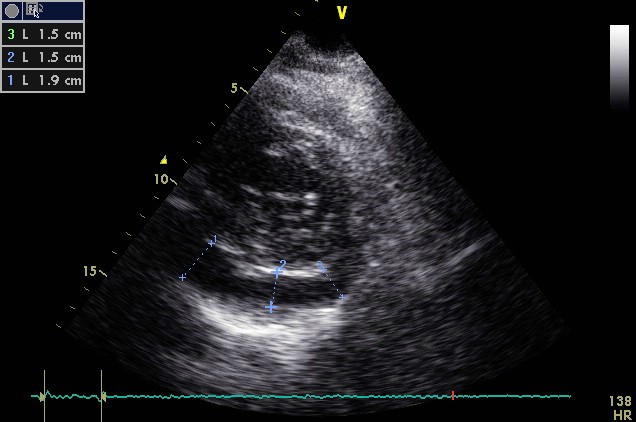

Echocardiography is low cost, widely available and can be performed on an urgent basis. It provides valuable information regarding the thickening and hyperechogenicity of pericardial layers, the presence or absence of pericardial effusion, its volume and its concomitant haemodynamic effects (tamponade, restriction). [6,16] Pericardial effusion, either new appearing or worsening, is typically mild and is evident in 60% of cases (Figure 2). [6] With the use of the M-mode, pericardial effusion is demonstrated as an echo-free space between the inner and outer layer of pericardium at cardiac systole and diastole, whereas a simple systolic separation may be considered physiologic. [1] Pericardial effusion, based on the size at diastole, is characterised as mild (<10 mm), moderate (10-20 mm), or large (>20 mm). [1] Unfortunately, TTE may exhibit a number of limitations, such as poor acoustic window due to obesity or chronic obstructive pulmonary disease (COPD), limited tissue characterisation, and a relatively high dependence on the operator. [17] That is why several other imaging techniques have evolved during recent years assisting in the diagnostic workup of patients with pericarditis.

Figure 2. The Echocardiographic Examination (parasternal short-axis view) of a 60-Year-Old Woman with Acute Pericarditis Reveals Echo-Free Space (>1 and <2 cm) Located Posteriorly, Suggestive of Moderate Pericardial Effusion